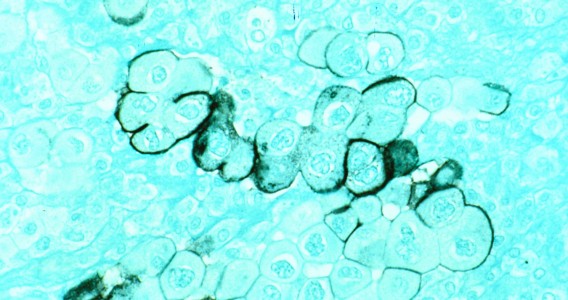

El virus de la COVID-19 manipula el ARN de la célula huésped para desactivar el sistema inmunitario

Un estudio de la Universidad Federal de São Paulo describe cómo el SARS-CoV-2 interactúa de manera inédita con el ARN de las células pulmonares infectadas; los resultados pueden orientar la búsqueda de nuevos tratamientos y vacunas